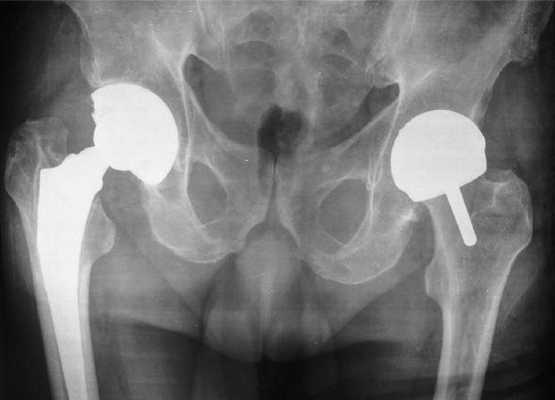

Двухсторонний коксартроз, обратите внимание на симметричное отсутствие суставной щели обоих суставов.